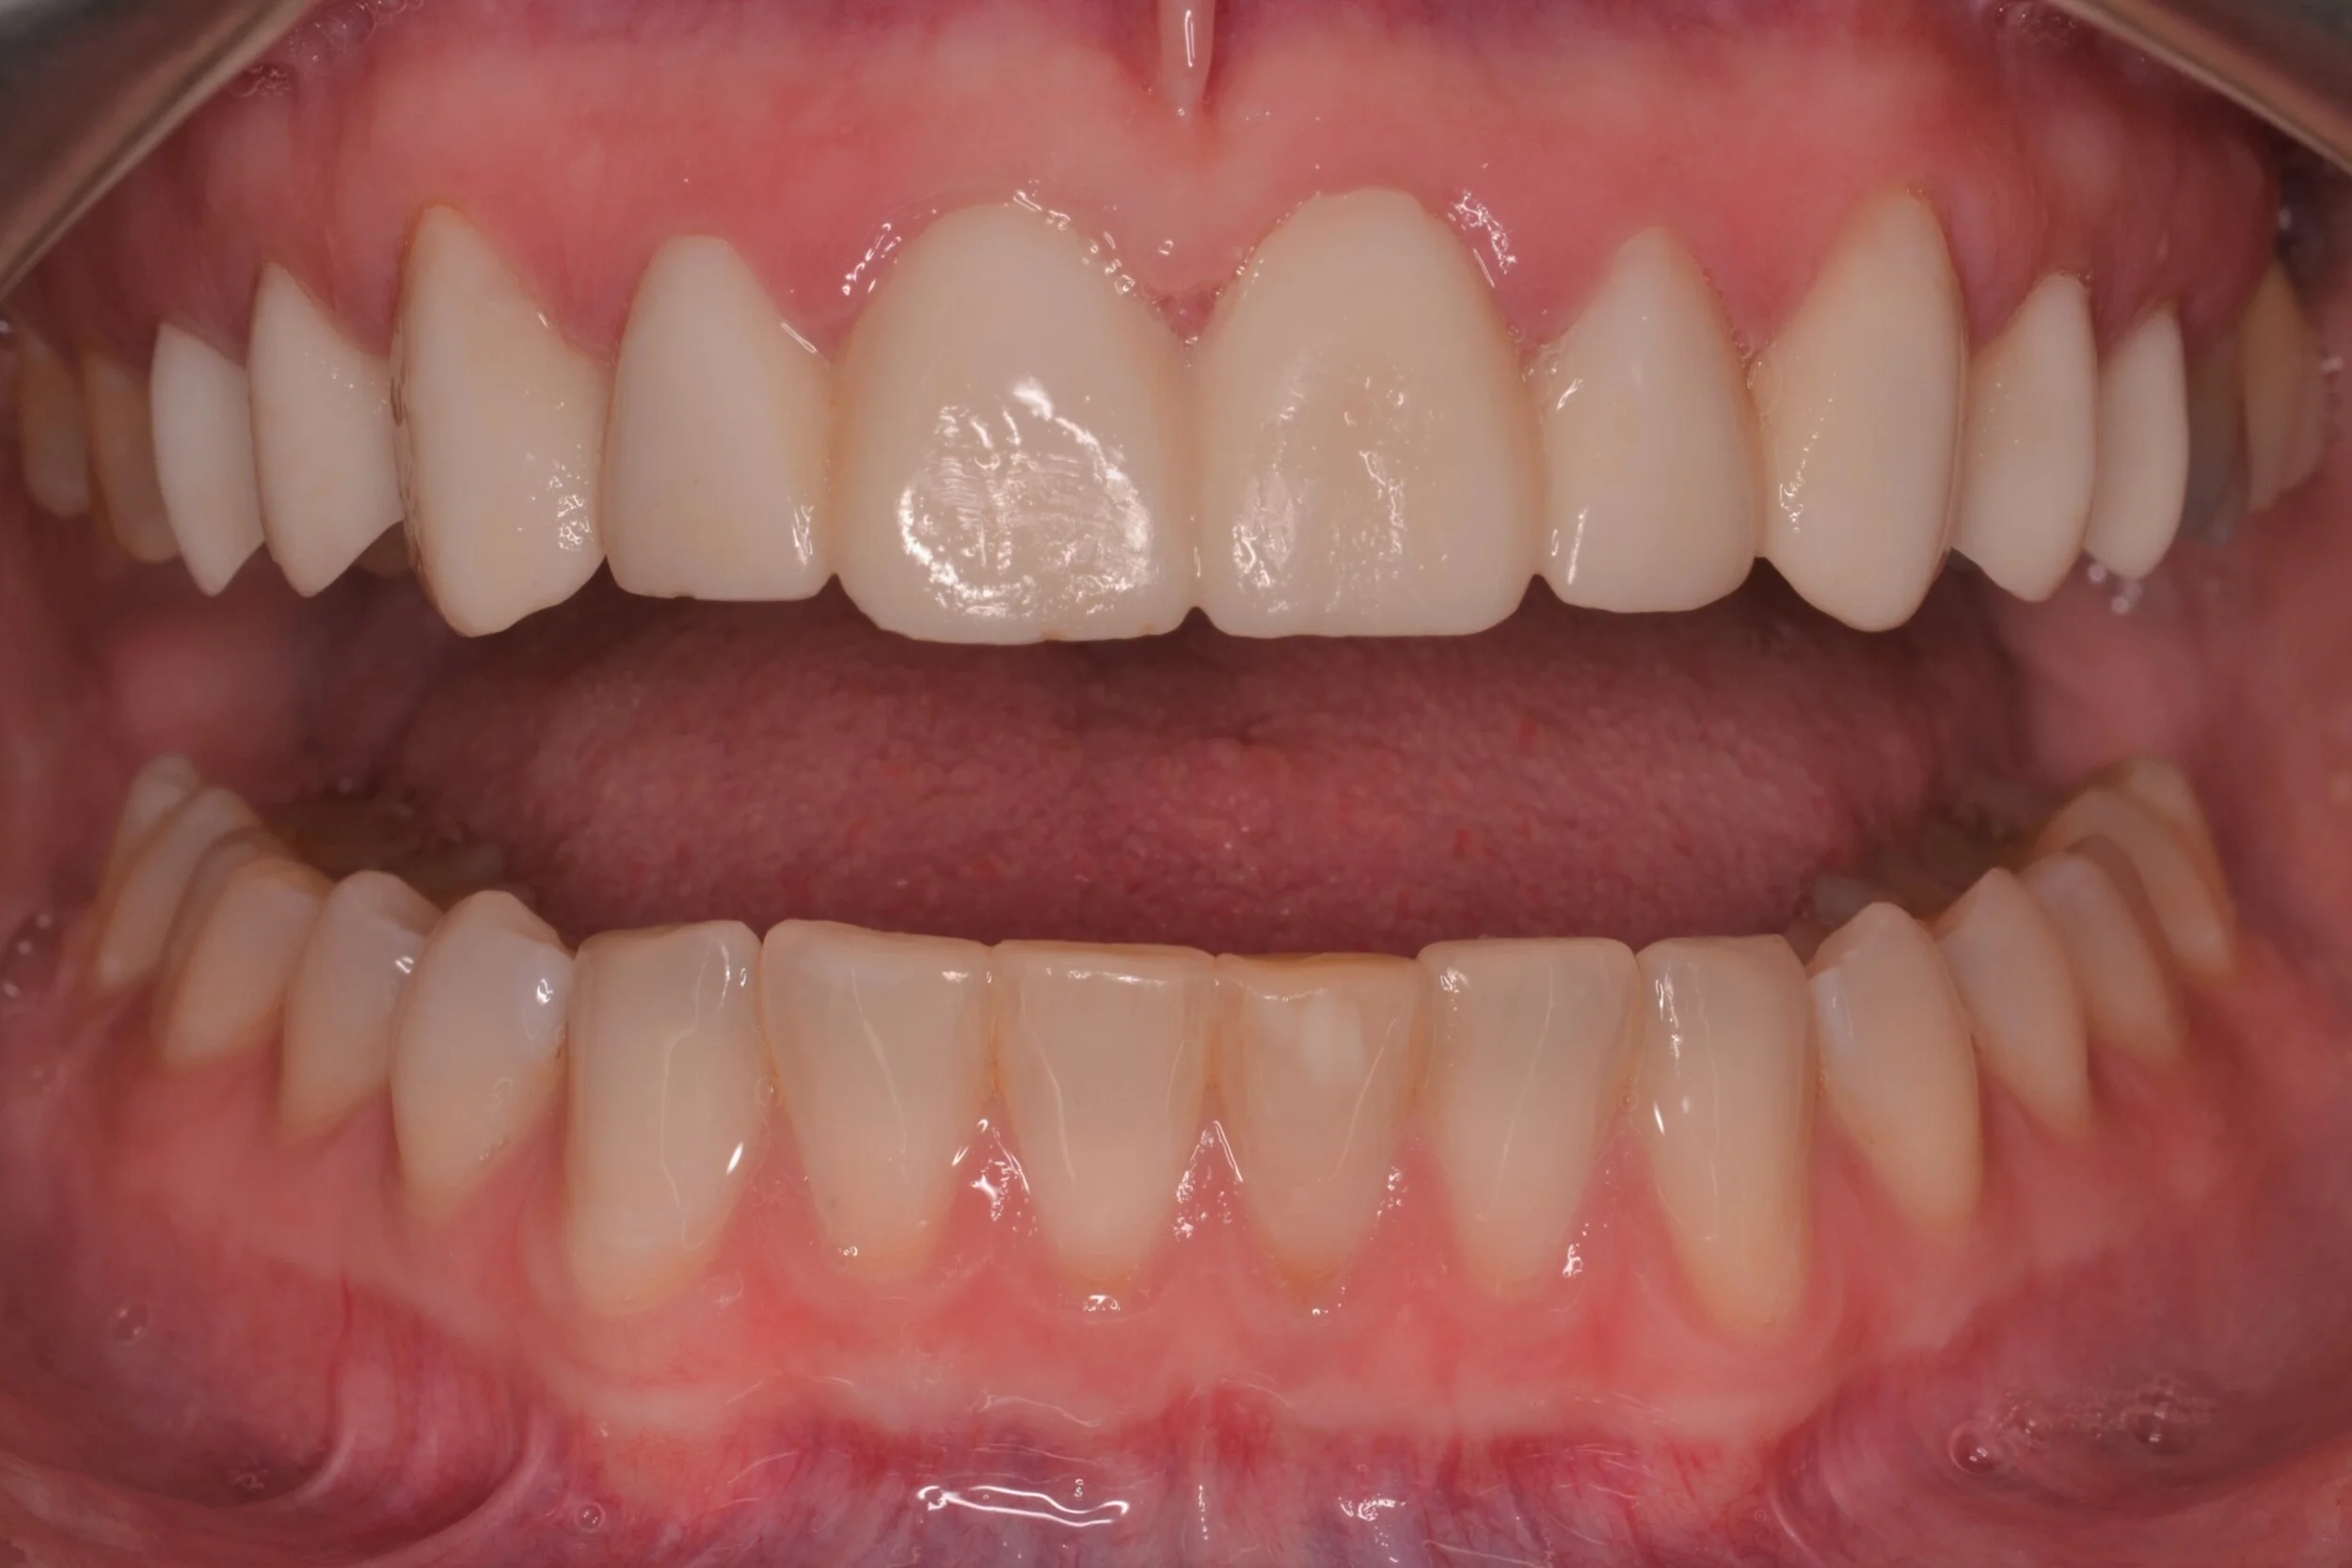

Figure 1; Presentation of patient and provisionals at delivery appointment

The importance of home-care and dental hygiene instructions for the duration of the provisional use is paramount, as an isolated field free of heme and debris is supremely advantageous for inserting cosmetic ceramic restorations with an adhesive bonding technique. Fortunately, the patient in this case was able to maintain good oral hygiene and presented with healthy gingiva that showed little to no sign of inflammation (figure 1). In cases where gingival inflammation will create heme that will interfere with adhesive bonding techniques, placing retraction cord in the gingival sulcus must be considered.